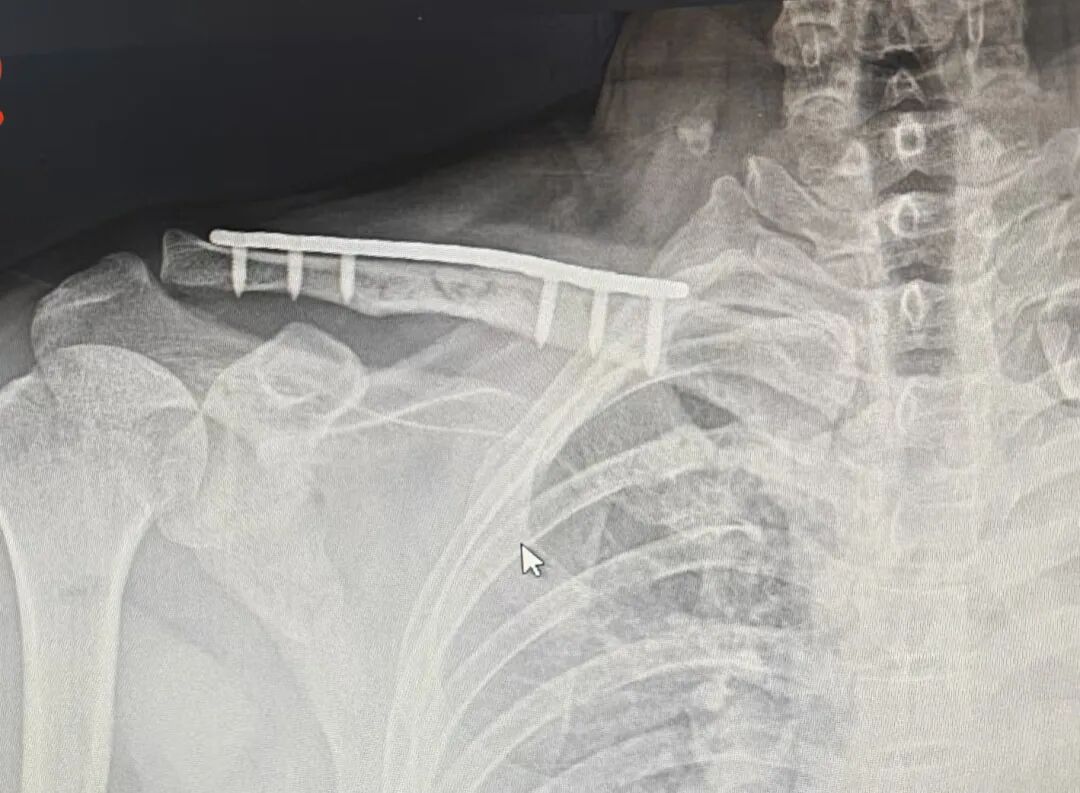

术后第五个月

钢板断裂

骨折也没有愈合

钢板断裂原因?

回头看第一次手术

钢板和骨折复位都挺好啊

怎么就断了